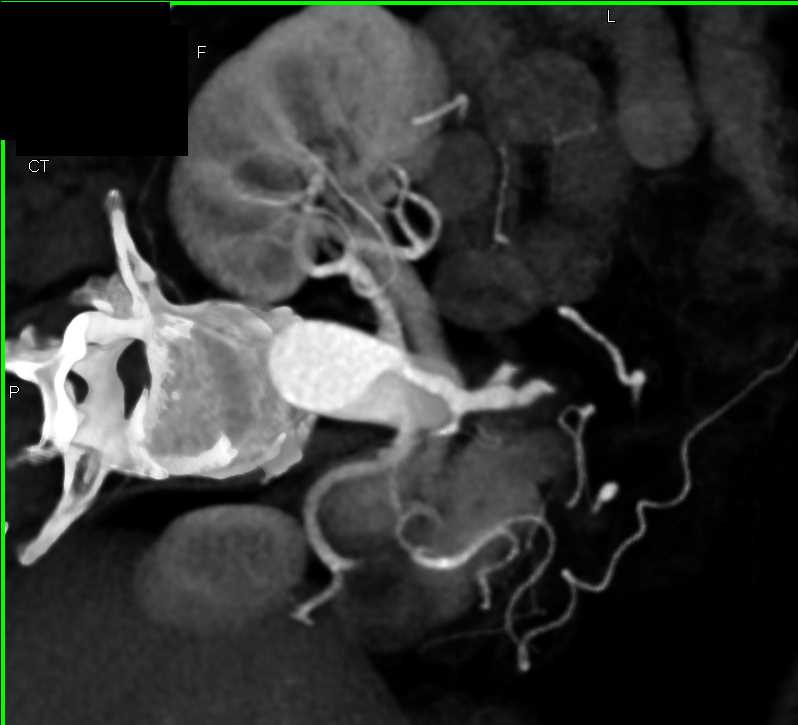

Neuroendocrine Tumor Body of Pancreas